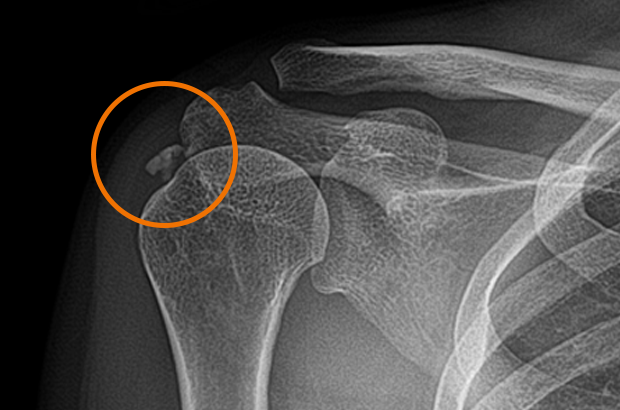

석회

회전근개 힘줄 안에서 발생 석회가 있었다는 것은 이미 수 년동안 회전근개쪽에도 문제가 있었다는 것을 의미

석회의 상태

형성기

석회가 분필처럼 말라서 딱딱하게 굳어져있는 상태흡수기

석회가 치약처럼 말랑말랑해져 있는 상태치료 방법